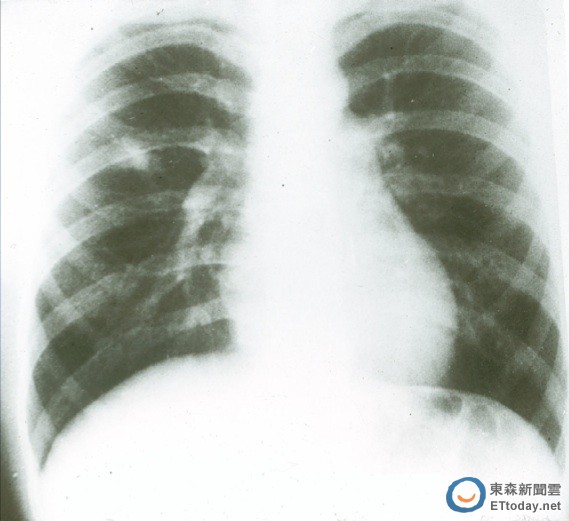

肺炎向來是國人十大死因的兇手之一,根據衛福部2014年統計,肺炎高居第四名且成長最快,相較2013年,比例增加近一成。在國外,不少名人也都死於肺炎,例如,諾貝爾和平獎得主南非總統曼德拉、新加坡前總理李光耀,以及最近的美國搖滾歌手老鷹合唱團主唱Glen Frey。

這個主要由細菌感染造成的疾病,治療的方式以抗生素為主,但目前碰到的問題是許多細菌已經形成抗藥性,相對地也讓肺炎治療更為棘手,因此,美國、歐盟,以及世界衛生組織(WHO)都紛紛提出警告希望遏止抗生素濫用的問題,並呼籲致力於研發新型抗生素。